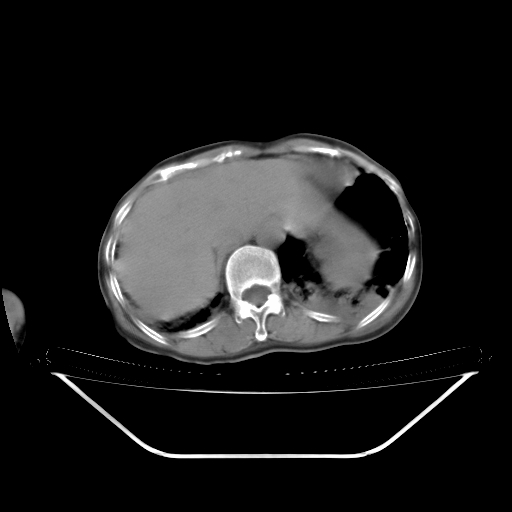

女70 反复咳喘心悸10余年,再发加再重伴双下肢浮肿8天入院。有肺结核病史20余年。

临床诊断:copd

双肺弥漫性间质性改变,内夹杂斑片状影,考虑肺水肿伴感染可能性大。右胸廓塌陷,右胸膜增厚粘连,心包积液

1)考虑间质性肺炎。2)右肺上叶结核并右肺上叶肺不张,右肺上叶支气管内膜结核不排除;两肺门及纵隔多发淋巴结钙化。3)心包积液;冠状动脉钙化。

1双肺间质性改变伴磨玻璃状影,考虑肺水肿伴感染可能性大。2心包积液。冠状动脉钙化。3右胸廓塌陷,右胸膜增厚粘连.

右肺支气管内膜明显增厚 变窄,并凹凸不平,右肺内见广泛的渗出 结节及斑片状混杂阴影。左肺下叶胸膜下渗出性致密影,双侧渗出影局限在双肺下部。另:左侧胸腔少量积液,心包肥厚伴积液。心脏增大。右侧陈旧胸膜病变伴胸廓塌陷,纵隔淋巴结钙化。多考虑:1 心源性肺水肿伴肺内感染 心包积液 肺淤血。2 右肺支气管内膜癌伴肺泡转移不除外。3 陈旧结核!